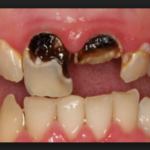

Кариес корня зуба фото

Кариес на корне зуба визуально практически никогда не определяется. Очень редко, и лишь в случаях, когда зубной камень значительно опустил ткани десны, может быть видно темное пятно или изъязвленный участок эмали. Чаще всего кариесом развивается на корнях передних нижних зубов и в межзубном промежутке. Во втором случае можно заметить снижение высоты десневого сосочка и увеличение межзубного промежутка в самой нижней его части.

Кариес корня зуба всегда развивается в качестве осложнения пришеечной формы заболевания или кариеса, образовавшегося под десной. Эти разновидности болезни, в свою очередь, имеют собственные источники. Как правило, это твердый зубной налет. Длительное присутствие на зубе минерализованных отложений со временем приводит к их опущению вниз, по направлению к десне и под нее, к шейке зуба. Анатомически эта часть зуба наименее защищена — слой эмали очень тонкий, что позволяет болезни намного быстрее разрушить его и проникнуть в ткани дентина.